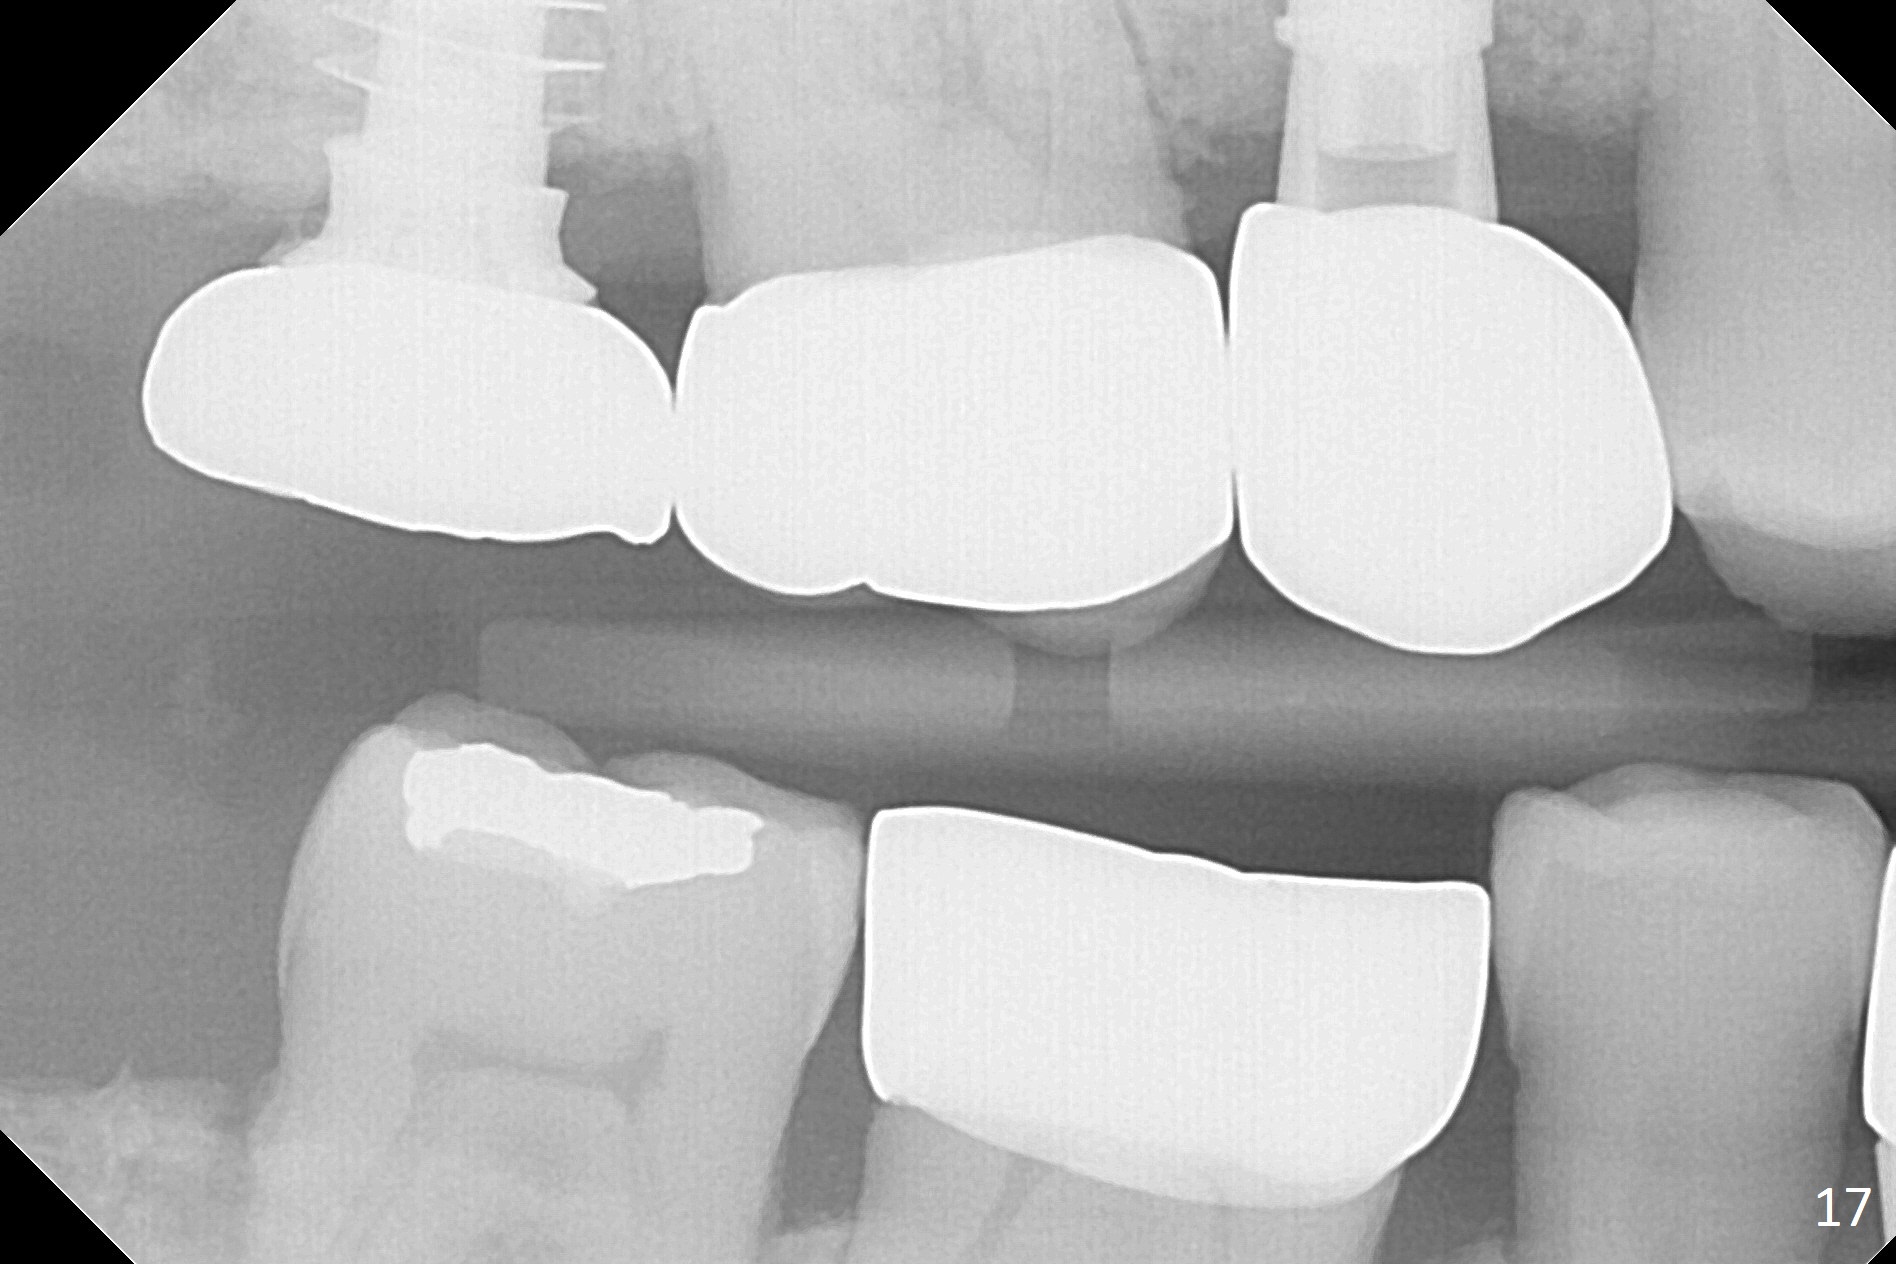

The right posterior final restorations (Fig.14) are fabricated as planned: increase in vertical height (Fig.15). The increase is minimal (Fig.14, 17(#2 limited crown height), 16 (#2 crown being thin *)). Fig.17,18 are taken immediately post cementation. There is no bone loss 10 months post cementation (Fig.19,20). The gingiva is healthy around the implant crowns (#2, 4 and 28) 1 year 4 months post cementation (Fig.21,22).